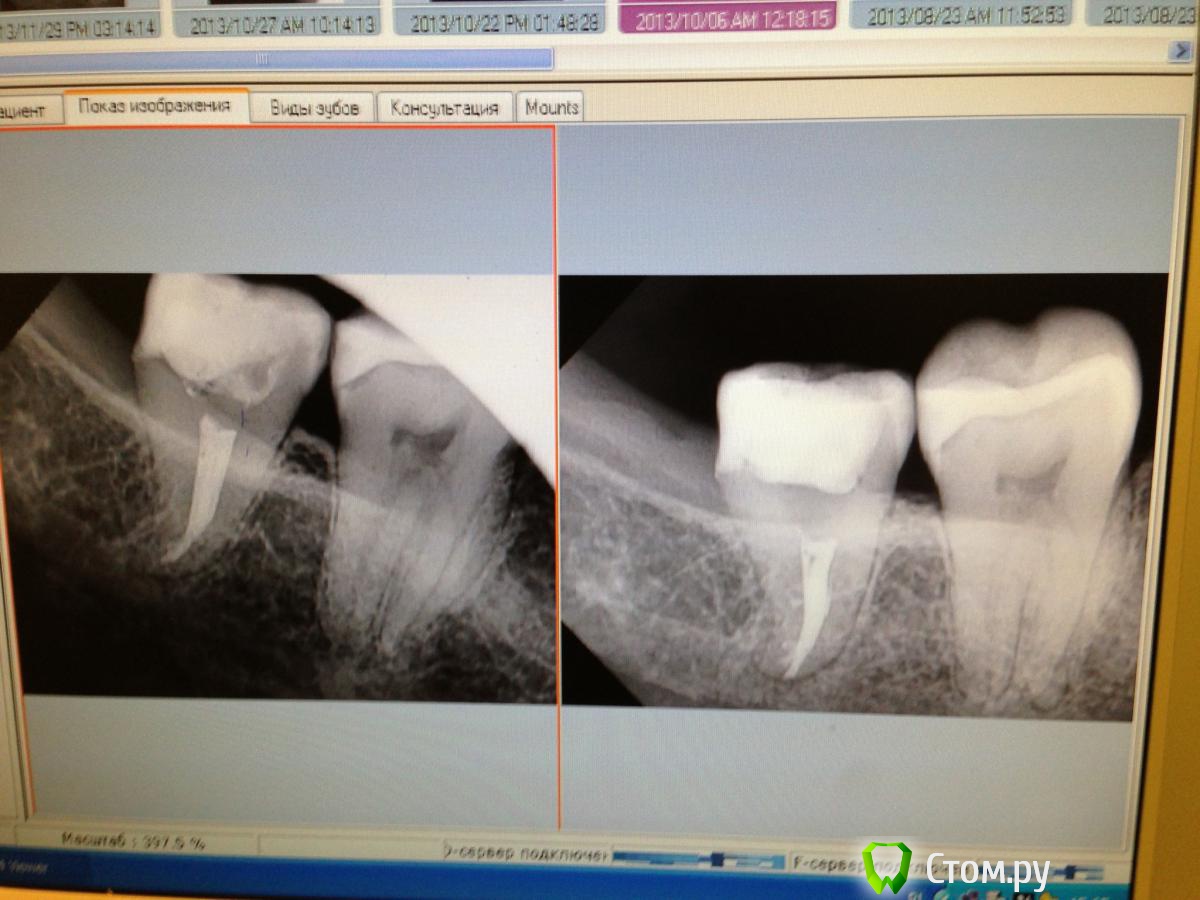

diesel87 Опубликовано 29 ноября, 2013 Поделиться Опубликовано 29 ноября, 2013 (изменено) Не пойму что еще сделать, зуб 48, ранее лечен по поводу пульпита, начал беспокоить, распломбировал канал, ввел метапекс, через неделю беспокоит при накусываем именно верхней восьмеркой, когда пациентке хочется на него постучать или когда щеткой электрической чистит, от вибрации боль не большая, пришла сегодня, прошел месяц, тоже самое... Изменено 29 ноября, 2013 пользователем diesel87 Ссылка на комментарий

АнтонТЛТ Опубликовано 29 ноября, 2013 Поделиться Опубликовано 29 ноября, 2013 (изменено) Так я говорю, что там транспортация апекса. Посмотри снимок до лечения, там канал дистально уходит, а у тебя перфорация Изменено 29 ноября, 2013 пользователем АнтонТЛТ Ссылка на комментарий

Kivilgar Опубликовано 29 ноября, 2013 Поделиться Опубликовано 29 ноября, 2013 Не пойму что еще сделать, зуб 48, ранее лечен по поводу пульпита, начал беспокоить, распломбировал канал, ввел метапекс, через неделю беспокоит при накусываем именно верхней восьмеркой, когда пациентке хочется на него постучать или когда щеткой электрической чистит, от вибрации боль не большая, пришла сегодня, прошел месяц, тоже самое...image.jpgА там не могли быть пародонтологические причины- ну там травма десны, сосочка, постоянное застревание пищи? Я как бы по снимку не вижу причины для таких болей. Непонятно. Вот такие ситуации когда все вроде бы ровно с зубом, а оно болит- вымораживают. Ссылка на комментарий